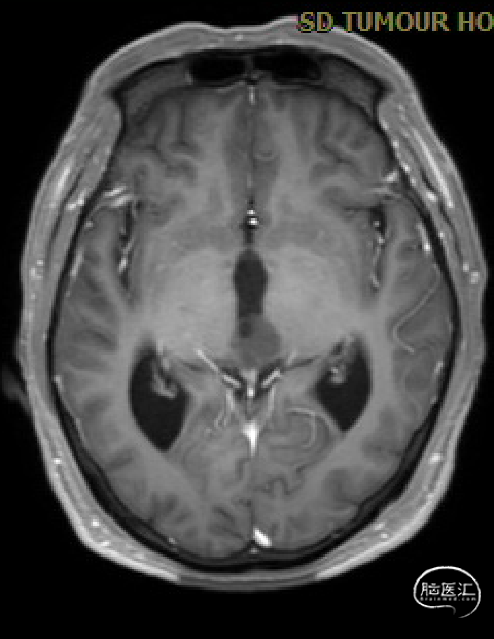

患者5年前无明显诱因出现阵发性头晕,无明显头痛、恶心呕吐等不适,开始未予重视,2022-7-19出现头晕加重,伴视力下降,遂于2022-7-24在当地医院行颅脑MRI提示:松果体区肿瘤伴梗阻性脑积水。

术前MRI与术后复查MRI对比